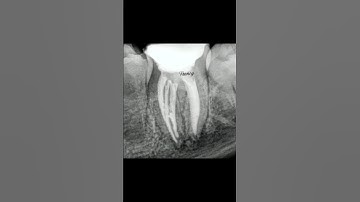

MTA APEXIFICATION | Mandibular First Molar | Apexification Step by Step